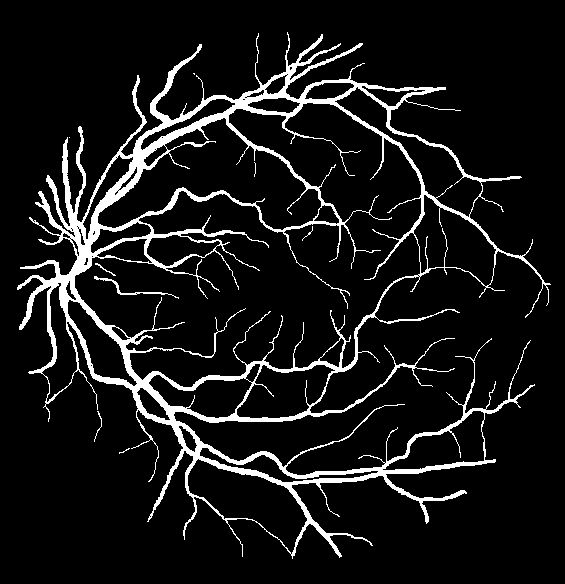

VI-A Retinal Artery and Vein Segmentation

As reported in Table IV, we compared the SegRAVIR model against competing deep learning-based segmentation approaches on the RAVIR dataset. Evidently, SegRAVIR outperforms these methods as judged by all metrics for artery and vein classes with a healthy margin. In terms of Dice score, SegRAVIR outperforms CE-NET, IterNet and AG-Net by , and for artery segmentation and by , and for vein segmentation, respectively. Fig. 4 presents a qualitative comparison of the semantic segmentation outputs of SegRAVIR, CE-Net, and U-Net. Specifically, SegRAVIR yields more accurate vessel topology (i.e., thickness and orientation) segmentation with higher pixel-wise classification accuracy.

Table V presents quantitative performance benchmarks of SegRAVIR and other competing approaches for retinal artery and vein classification on the RITE dataset [11]. SegRAVIR outperforms previous state-of-the-art approaches in terms of accuracy, sensitivity, and specificity. Fig. 5 provides a qualitative comparison between segmentation outputs of SegRAVIR and the method of Hemelings et al. [40] on the RITE test set.